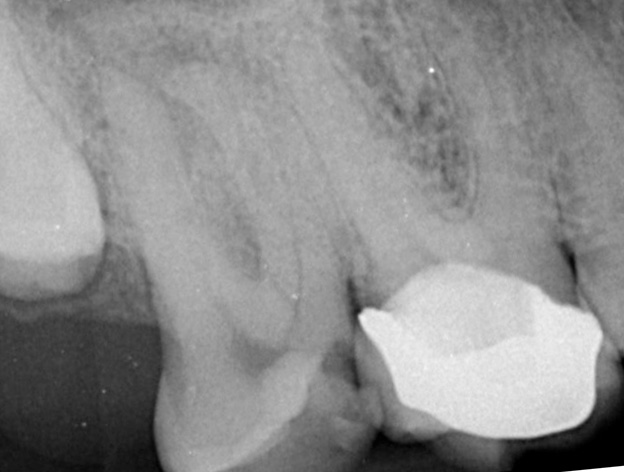

- Protection is Key: Once the tooth has settled down following the endodontic treatment, a crown should be placed to protect the remaining tooth structure from fracture. This is necessary to ensure the longevity of the tooth.

Once the root-treated tooth has settled down completely, a crown should be placed to protect the remaining tooth structure from fracture. This protective crown is necessary to ensure the longevity of the tooth, which can then last for many years.